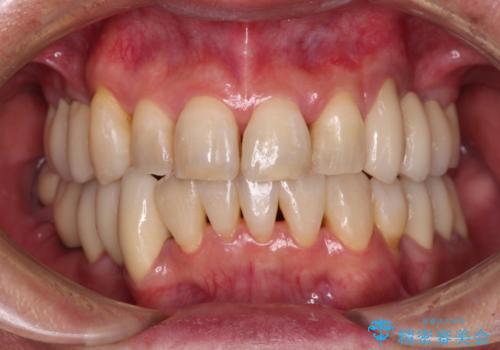

- 口元のデコボコを気にして来院された患者様です。

前歯の捻れにより口元が閉じにくくなっていたため、歯列全体の側方への拡大と、歯と歯の間を少し削ってスペースを獲得することとしました。

ゴムかけをしっかりと行ってもらい、スッキリとした口元に仕上げることができました。